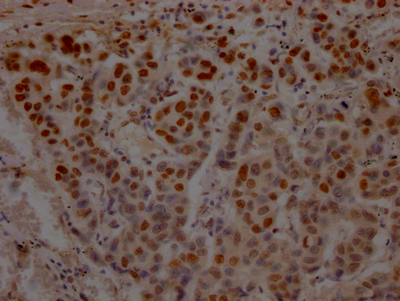

IHC image of CSB-RA214807A0HU diluted at 1:100 and staining in paraffin-embedded human breast cancer performed on a Leica BondTM system. After dewaxing and hydration, antigen retrieval was mediated by high pressure in a citrate buffer (pH 6.0). Section was blocked with 10% normal goat serum 30min at RT. Then primary antibody (1% BSA) was incubated at 4℃ overnight. The primary is detected by a Goat anti-rabbit IgG polymer labeled by HRP and visualized using 0.05% DAB.

產(chǎn)品描述:CSB-RA214807A0HU TP53重組單克隆抗體是針對腫瘤抑制蛋白p53研發(fā)的高特異性檢測試劑。該抗體通過重組技術(shù)制備,靶向人源TP53基因編碼的p53蛋白,該蛋白作為關(guān)鍵的細(xì)胞周期調(diào)控因子,在DNA損傷修復(fù)、細(xì)胞凋亡及腫瘤發(fā)生中發(fā)揮核心作用。經(jīng)嚴(yán)格驗證,本產(chǎn)品在ELISA實驗中表現(xiàn)出優(yōu)異的抗原結(jié)合能力,同時在免疫組化(IHC)應(yīng)用中可清晰顯示組織樣本中p53蛋白的定位表達(dá),推薦使用稀釋比為1:50-1:200時能獲得理想染色效果,適用于石蠟包埋組織切片分析。其高親和力與低交叉反應(yīng)性特點,使其成為研究腫瘤發(fā)生機(jī)制、細(xì)胞應(yīng)激反應(yīng)通路及基因功能調(diào)控的可靠工具,尤其適用于癌癥相關(guān)基礎(chǔ)研究中的蛋白表達(dá)模式分析、病理模型構(gòu)建及分子互作實驗。本抗體采用單克隆重組技術(shù)生產(chǎn),具有批次間高度一致性,可在-20℃長期穩(wěn)定保存,建議分裝后避免反復(fù)凍融以維持最佳活性,為科研工作者提供穩(wěn)定高效的檢測支持。

Application Recommended Dilution IHC 1:50-1:200 -